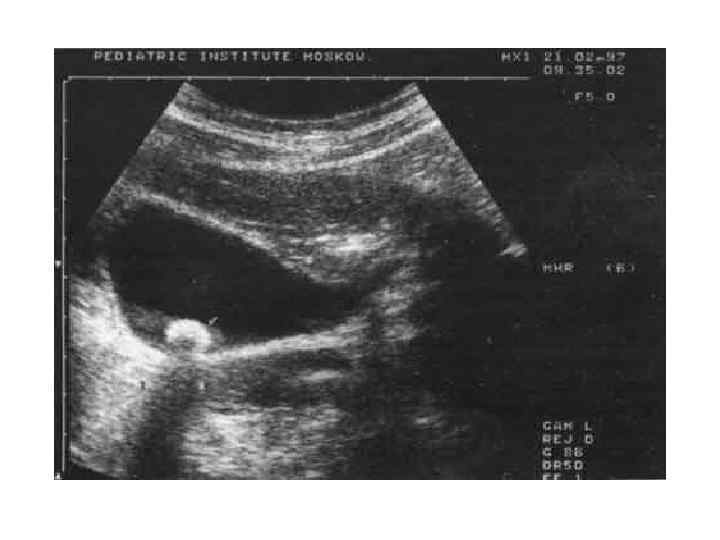

Клинико-физиологические методы изучения пищеварительной функции печени • Химический анализ дуоденального содержимого • Визуализирующие методы (ультразвуковые, радионуклидные, рентгенологические ? )

Клинико-физиологические методы изучения пищеварительной функции печени • Химический анализ дуоденального содержимого • Визуализирующие методы (ультразвуковые, радионуклидные, рентгенологические ? )